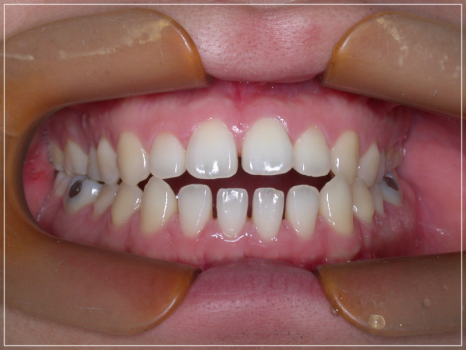

앞니가 안 다물어지는 상태를 개선한 모습

협조도가 저조하거나 근육의 적응력이

뒷받침되어 주지 않는다면 문제를

개선하는데 있어 분명한 한계점이

존재한다는 단점도 가지고 있습니다.

때문에 퇴행성 턱관절염으로 인해

개방교합이 발생한 경우에 해당된다면

위의 과정은 적합하지 않기에

다른 방법을 고려해보셔야 했는데요.